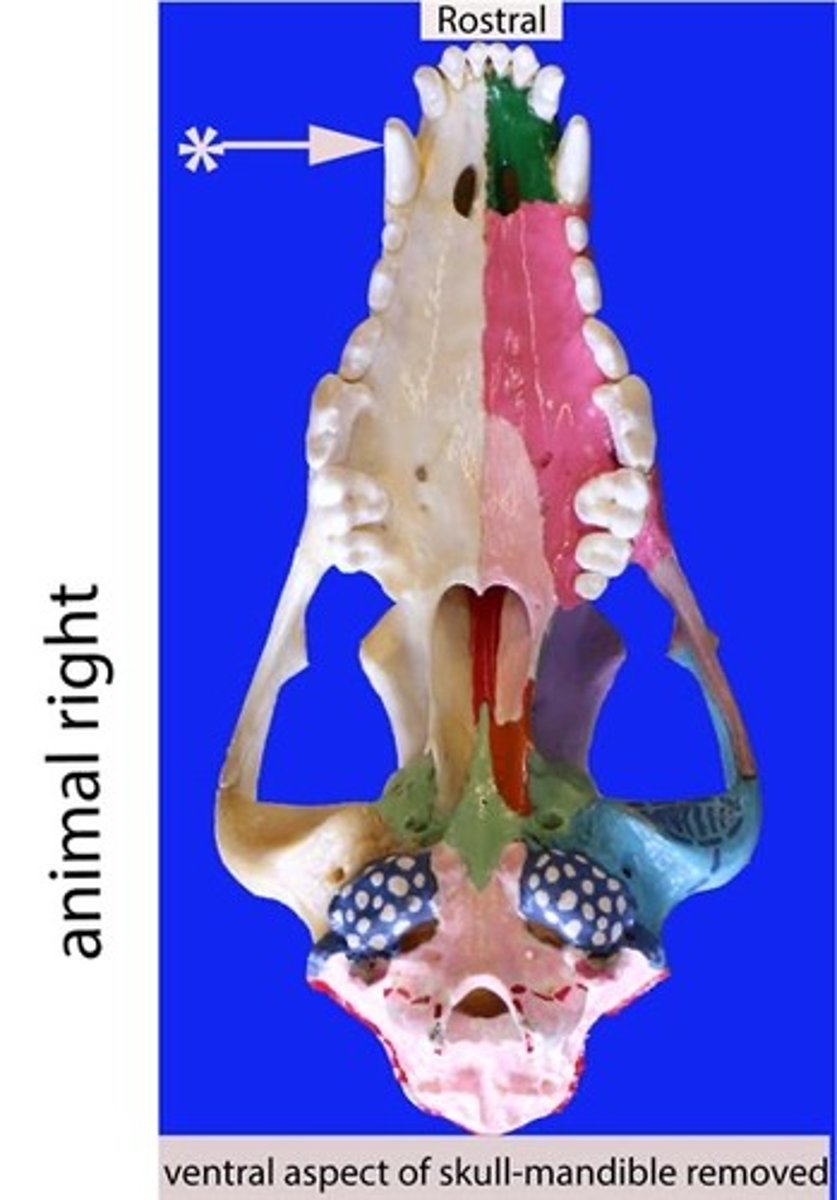

canine

Identify the general type of tooth the arrow is pointing to

Canines

Identify the type of teeth shaded.